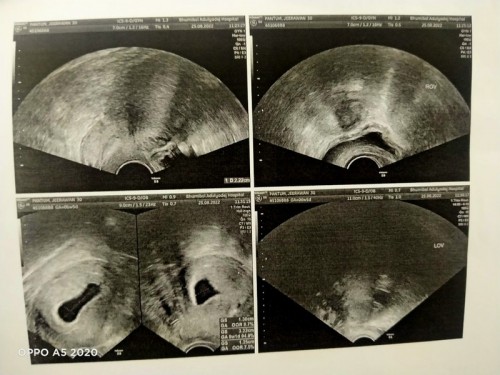

ไปซาวด์มา6วิค6วันแต่ไม่เจอตัวอ่อน

และหัวใจของเด็กใครเคยเป็นแบบนี้บ้างคะหมอนัดอีกสองอาทิตย์ไปซาวด์ใหม่ถ้าไม่เจอน้องเขาจะยุดติการตั้งครรภ์นั้นหมายความว่าท้องลมแม่เคียดมากๆๆ

บ้านนี้ไปตรวจ ตอน 6 วีคค่ะ เจอถุงตั้งครีภ์ กับถุงไข่แดง หมอก็ไม่ว่าอะไรนะคะ นัดอีกที 2 สัปดาห์ เจอค่ะเเม่ พร้อมหัวใจเต้นแล้ว

เราซาวด์ 6w5D เจอตัวน้องหางยาวมากก วัดขนาดหัวถึงก้น 0.75 cm หัวใจเต้น 133 ครั้งต่อนาทีค่ะ

บ้านนี้เหมือนกันค่ะ ไม่เจอน้อง เจอถุงตั้งครรภ์กับไข่แดง แอบกังวลนิดๆๆ